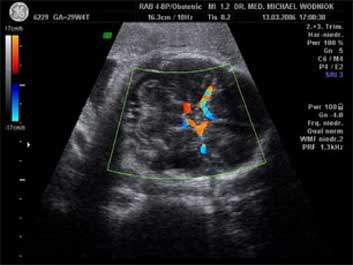

Unterscheidung zwischen dem anlagebedingt kleinen (nicht gefährdeten) und dem minderversorgten (gefährdeten) Kind. Der Nachweis einer chronischen Mangelversorgung des Kindes durch eine nicht ausreichende Funktion des Mutterkuchens (Plazenta) gelingt mit der Dopplersonographie durch die Messung der Blutströmungsverhältnisse in der Nabelschnurarterie und Gehirnarterie des Kindes mit de Dopplersonographie.